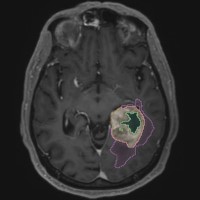

Das Modul Tumordifferenzierung ermöglicht eine automatisierte Differenzierung von Tumorkern und Randödem detektierter Gliome. Auch ist eine direkte Schnittstelle zu Strahlentherapie- und Neurochirurgie-Software möglich.#Kopf #Gehirn